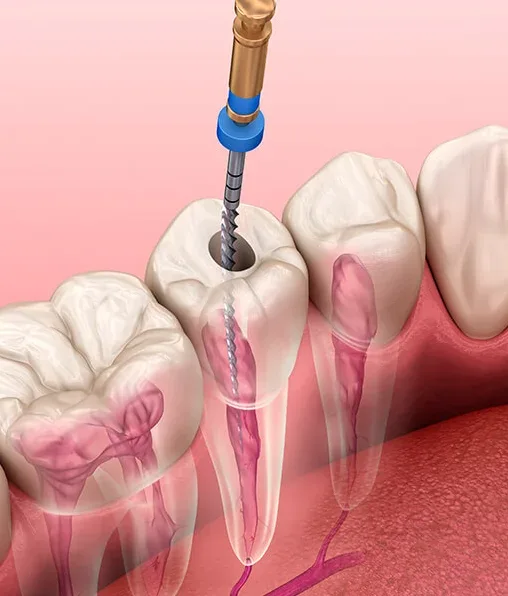

O consultório endodontia oferece uma série de benefícios cruciais para a longevidade da saúde dental. Este espaço é especializado em tratar problemas que afetam a polpa dentária, sendo a solução definitiva para quem sofre com dores intensas e quadros infecciosos.

Buscar o suporte de um consultório endodontia permite que o paciente elimine focos bacterianos de forma precisa. Através de técnicas modernas, a saúde bucal geral é aprimorada, estabelecendo um ambiente biológico muito mais saudável e protegido.

Um dos principais ganhos ao buscar o atendimento especializado é o alívio célere da dor. Pacientes que enfrentam quadros agudos encontram amparo imediato através de procedimentos que removem a polpa infectada, eliminando a fonte do sofrimento:

Fim do Desconforto: Neutralização rápida de dores pulsantes e sensibilidades extremas;

Tecnologia de Precisão: Uso de microscopia operatória e localizadores apicais para maior exatidão;